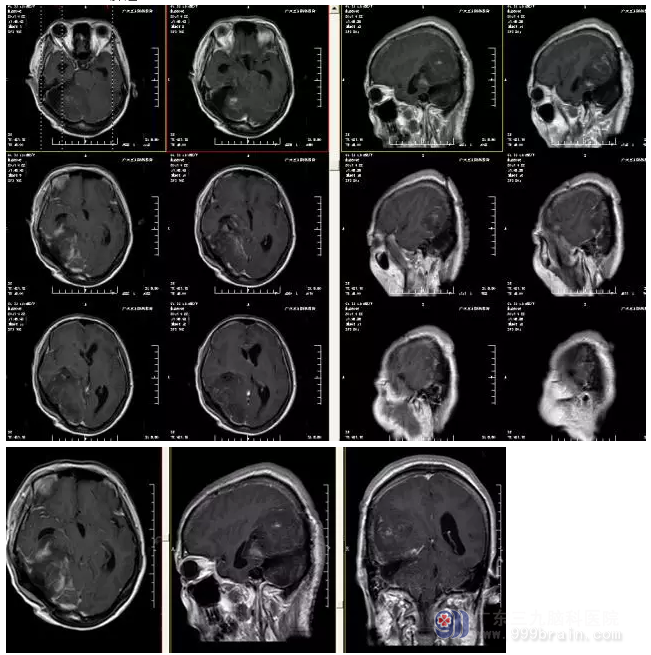

图4:术后MR显示肿瘤全切

中枢神经系统血管周细胞瘤的治疗以手术为首选,总体预后良好,但复发率高,手术全切可降低复发率,对手术次全切者有必要行放射治疗。中枢神经系统血管周细胞瘤血供丰富,发现时病变常体积已较大,切除时难度相对较大,本例病变体积巨大,CTA提示血供丰富,且与静脉窦关系密切,在手术中除重要神经血管的保护,还需特别注意直窦、横窦、乙状窦、大脑大静脉等重要血管的保护,术中注意止血,出血量少,未出现明确术后并发症,术后患者恢复良好。